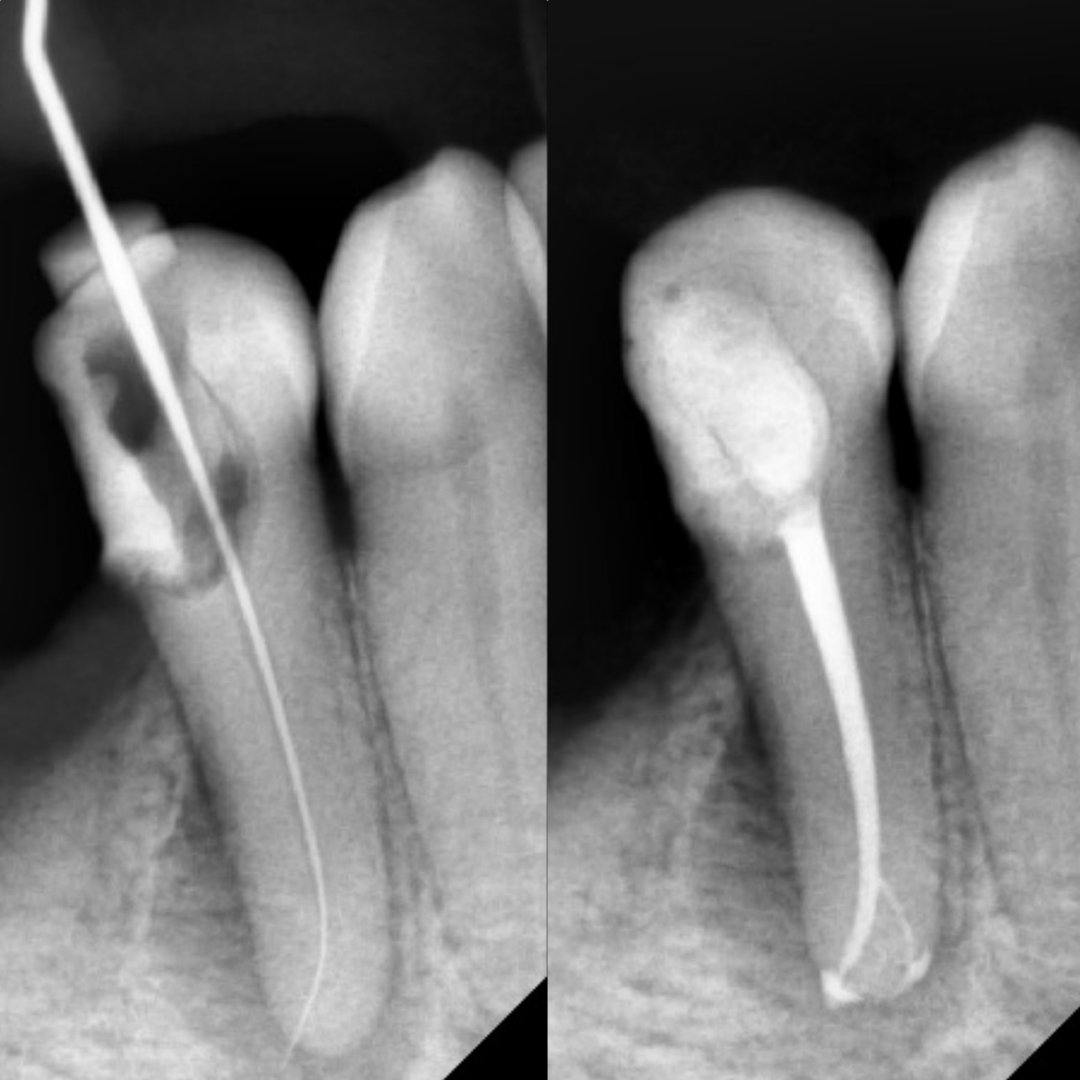

Before After Perawatan Saluran Akar (PSA) di Klinik Utama Pondok Gigi Jakarta

Transformasi nyata setelah perawatan saluran akar (PSA) di Klinik Utama Pondok Gigi Jakarta. Dari gigi rusak dan nyeri hingga kembali sehat dan berfungsi normal. Dikerjakan oleh dokter gigi profesional dengan teknik endodontik modern dan alat berteknologi tinggi untuk hasil maksimal.